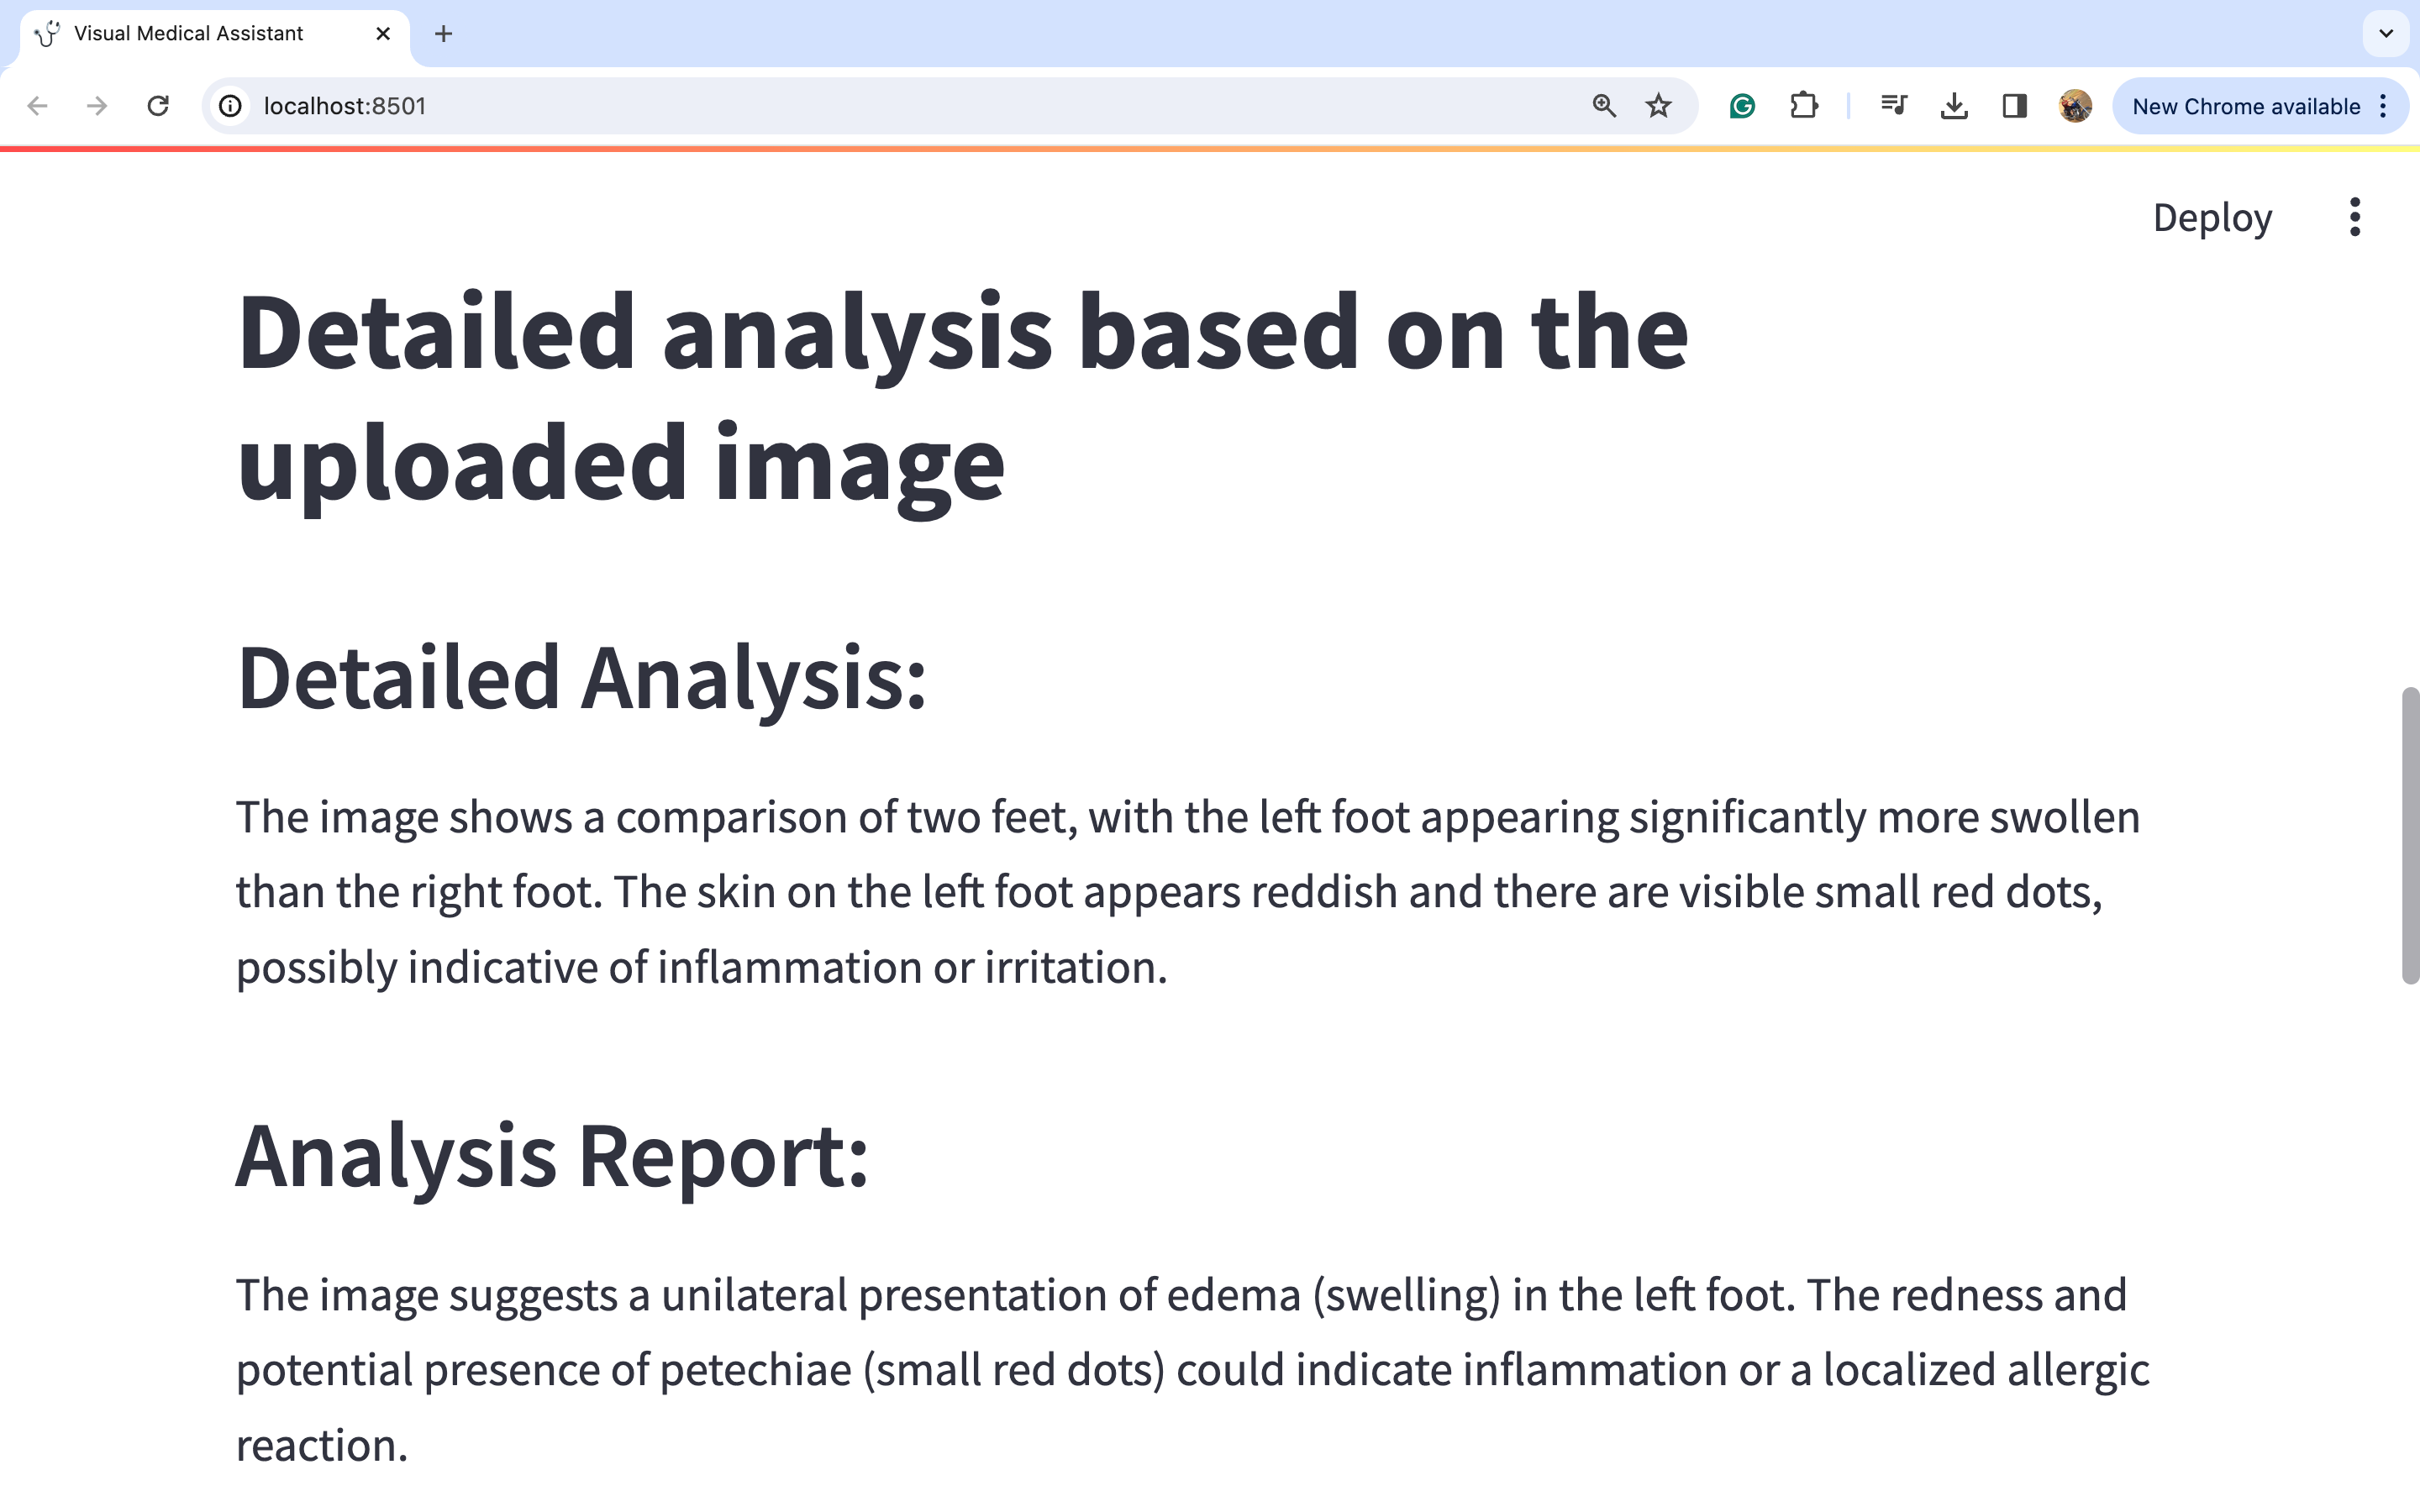

图片1:

因此,我们可以通过观察图片来进行深入的详细分析,从而得出可能的医疗诊断。我们可以看到模型如何捕捉到左脚肿胀的问题。模型建议咨询医生,因为仅仅通过观察这种肿胀很难得出很多结论。然而,我们可以看到一些治疗选择,如使用压缩包和抬高左脚以减轻肿胀,在这种情况下似乎是合理的选择。